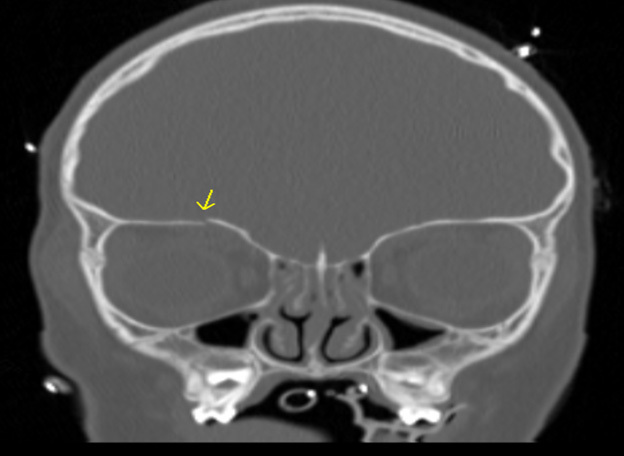

Figure 3 shows an example of an orbital roof fracture in a pediatric patient in the coronal plane. The image demonstrates a mildly displaced fracture.

Figure 3. Orbital Roof Fracture |

The image demonstrates a mildly displaced orbital roof fracture. Image courtesy of Mantosh S. Rattan, MD, Radiologist, Orlando Health Arnold Palmer Children’s Hospital, Orlando, FL. |